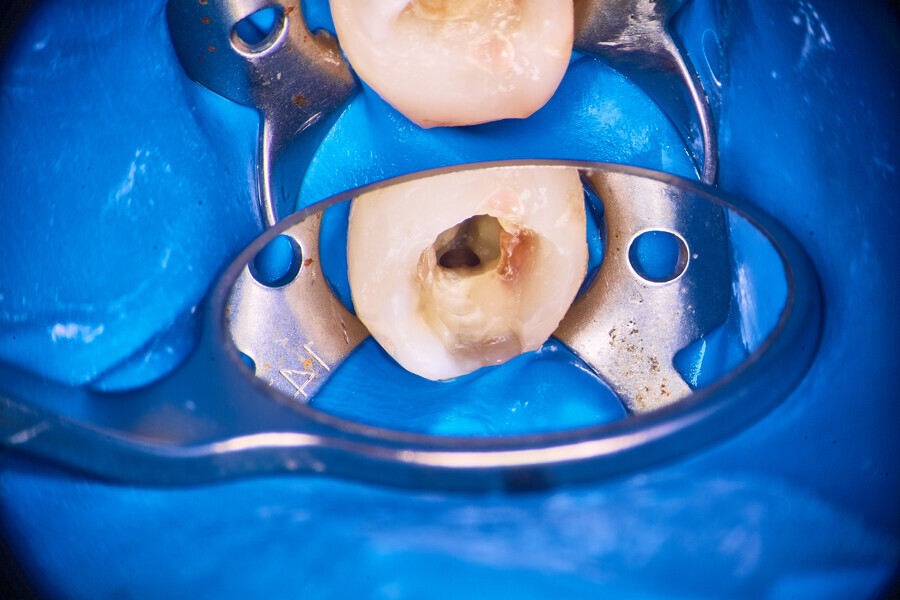

Once the pulp chamber floor is clean (Figs. 25 & 26), the mechanical instrumentation with endodontic rotary instruments can be done. In this case, instrumentation was done only with one instrument, the 12.5/0.04 R-PILOT file (VDW; Fig. 27). The decision to use only this file was determined by the complexity of the anatomy and risk of instrument fracture within this root canal space. After instrumentation with the in–out technique—which offers numerous advantages—and copious irrigation as well as laser-assisted activation of the irrigants between strokes, a final irrigation and activation protocol was performed using the Er,Cr:YSGG laser and RFPT5-10 tip (Figs. 28 & 29).

The canals were then ready for obturation (Figs. 30 & 31) and were obturated with the VDW.1Seal bioceramic sealer (VDW) using the cavit piston technique (Figs. 32–34). After obturation, a final postoperative radiograph was performed (Fig. 35).

Through laser-assisted endodontics, the operator was able to properly irrigate and obturate lateral anatomy normally impossible to reach with mechanical instrumentation. Owing to the velocity of irrigants activated with the Er,Cr:YSGG laser, minimal preparation was necessary to achieve clinical success.